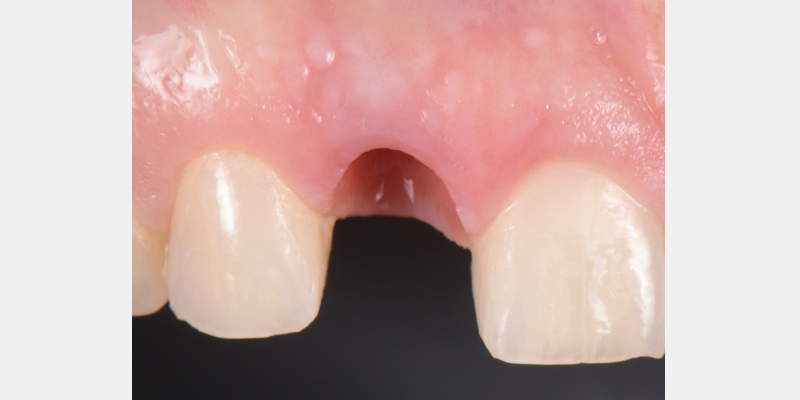

One of the most common complications with cement-retained implant restorations is inflammation around the crown. Excess cement can lead to peri-implant diseases such as peri-implant mucositis and even bone loss. A key factor to understand is the biological difference between teeth and implants — particularly the structure of the junctional epithelium and connective tissue — which makes removing residual cement around the restoration more difficult.

Here is a simple, step-by-step technique for fabricating a silicone jig to avoid excess cement in a cement-retained implant-supported restoration. It can be applied to a single crown or to an implant-supported cement-retained bridge.